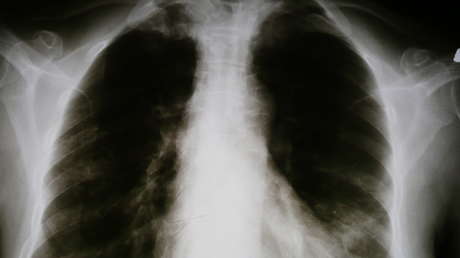

Investigadores de Google han desarrollado una tecnología, basada en aprendizaje automático, que permite detectar cuatro enfermedades pulmonares, afirma un artículo publicado el 3 de diciembre en la revista Radiology.

En particular, se trata de la detección de tres condiciones médicas vinculadas a los pulmones: neumotórax, nódulos y masas, y opacidad de espacio aéreo; además de fracturas de los huesos del tórax.

Por el momento, la tecnología, que se fundamenta en un conjunto de 600.000 imágenes de rayos X, ha alcanzado el nivel de precisión de un especialista humano, aseveran los autores del estudio.